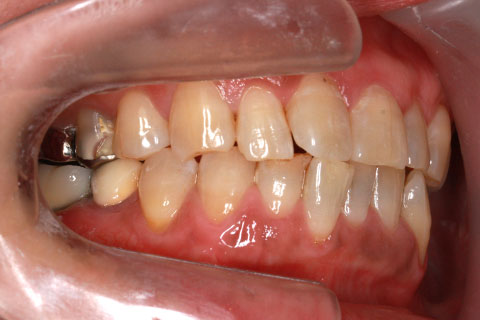

症例2

治療前

- 年齢・性別

- 57歳男性

- 治療期間

- 3ヶ月

- 抜歯

- なし

- 治療費

- 154万円

- 備考

- 左上5.6.7 及び左下6.7欠損

- 治療内容

- 左上5.6.7と左下6.7欠損部にインプラント埋入

- 施術の副作用(リスク)

- オペによる知覚障害。インプラントによる歯肉炎。インプラント脱落。